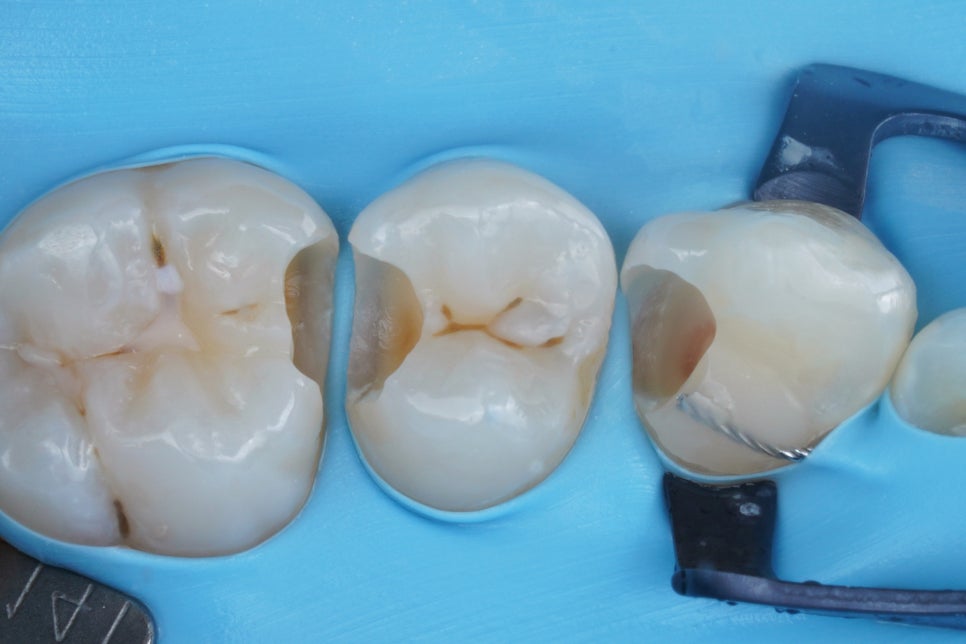

충치를 다 제거한 뒤에

<러버댐>을 끼워놓은 사진입니다.

바로 이렇게 러버댐만 ‘잘’ 써도

레진으로 치료가 가능해지는 것이었어요.

치아 삭제도 정확히 충치가 있는 부분만

타겟해서 진행했죠.

인레이는 이렇게 하지 못하고

레진으로 했다면 필요하지 않은 부분까지

광범위하게 삭제해야합니다.

그리고 보시다시피 고급 러버댐인

파란 ISO-DAM(이소댐)을 사용했는데요,

일반 러버댐과 소재 자체가 다릅니다.

내구성이 좋아 사용감이 좋고,

알러지반응도 없고

무엇보다 원칙적인 방습이 잘됩니다.

이번에도 교정 유지장치가 있어

어려울 뻔 했는데

좋은 클램프의 도움을 받았네요.

아무튼 레진 좀 한다는 치과의사들은

이렇게 '방습'이 잘 되었는지를

유심히 보고는 합니다.

레진의 퀄리티는 대개 이 때 좌우거든요.

치료할 부위를 정확히

잇몸과 피, 침, 습기로부터

완전히 '격리'시켰는가가

굉장히 중요한 치료 성공의 열쇠이기 때문입니다.